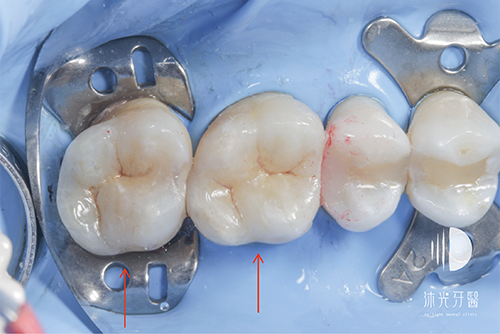

治療前